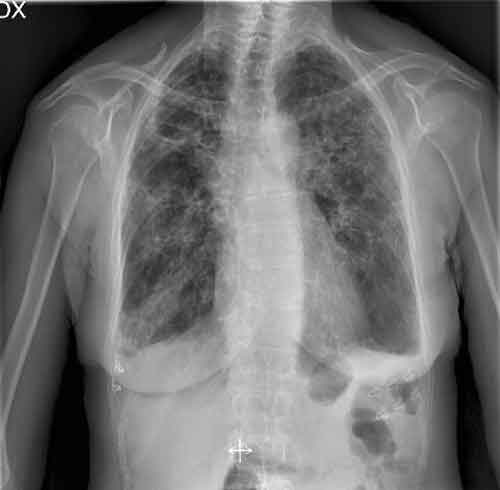

In Italia il fumo uccide oltre 70.000 persone ogni anno, di cui 30.000 solo per tumore al polmone. Se si considerano i 5.000 morti anno per incidenti stradali si capisce la rilevanza del problema. Nonostante le avvertenze sui pacchetti, 12 milioni di persone in Italia fumano circa 70 miliardi di sigarette l’anno. “L’epidemia da tabacco è la peggiore calamità che l’umanità si sia tirata addosso dopo le grandi pestilenze del passato”, conclude Mangiaracina.